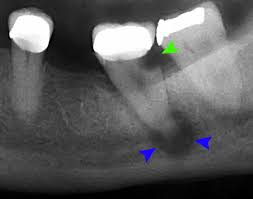

peri-implantitis

plaque biofilm-induced inflammation and progressive loss of alveolar bone

inflammation, bleeding and/or suppuration upon probing, increased probing depth, progressive bone loss, radiographic evidence of bone level >3mm, and/or probing depth >6mm

How often should radiographs be taken of dental implants

At least once a year